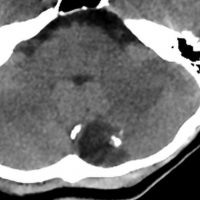

小脳類皮のう胞

偶然発見された女の子のものです。左のCTで石灰化があります。右の拡散強調画像 DWI で白く高信号に描出されるのが特徴です。手術では腫瘍内部に毛髪がたくさんありました。後下小脳動脈に強く癒着していて,脳軟膜からの剥離もできませんでしたが,完全摘出しました。無症状でも”完全”摘出 complete removal するべきです。